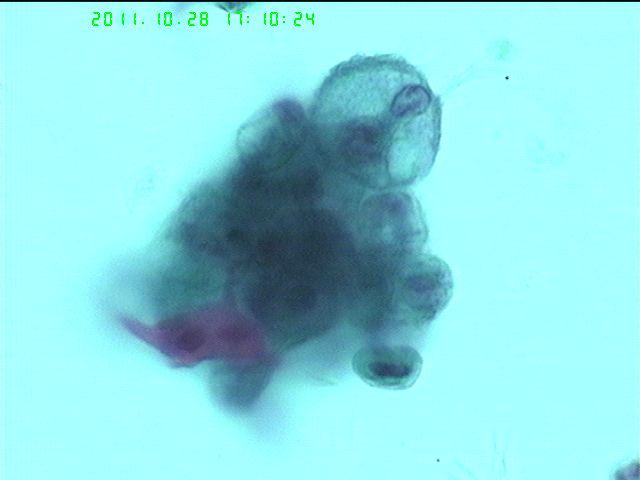

支刷液基   59岁  女性

请教图6和9是什么细胞?

请教图中的红染角化的细胞怎么判读?角化鳞癌细胞和退变、反应性的鳞状细胞如何鉴别?

非常漂亮的图片,支气管刷片的液基能做出这么漂亮真是难得。

6和9是鳞癌细胞。

判断角化鳞癌和退变的鳞状细胞还是应该从细胞的异型性,核浆比,核极性(非液基的看的清楚点),以及核染色质等综合考虑。

图片很漂亮,倾向于鳞状细胞癌!

第一次活检没夹到,顺便做了第二次支刷,大家考虑腺癌吗

我觉得第二次有些细胞还是鳞癌细胞,可以看到红染的角化的异型细胞,但有些细胞的确比较象腺癌,可以看到包浆内粘液空泡,大胆猜测下,可能是个腺鳞癌癌。

确定是癌细胞(类型,建议取活检再定,毕竟鳞、腺癌治疗有区别,别冒险)。

基本上同意老油老师的分析;如果遇到这种病例不像冒险的话;可以选择报:查见癌细胞,建议活检进一步明确分类。

活检结果:鳞癌。